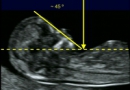

NT In first Trimester of pregnancy

nt1